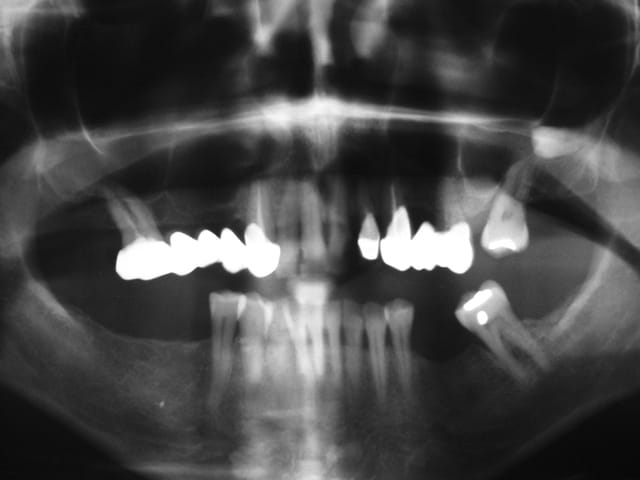

Patient qui tel, j’ai très mal sous le bridge que vous m’avais posé (23 24 25 en 2004, après dépose d’un bridge pour raison esthétique). Faut me voire aujourd’hui (lundi), elle arrive avec scanner des sinus fait en 2005, suite à des sinusites. Compte rendu du Radiologue, présence d'apex et d'Ag dans le sinus gauche, et que l’on peut rien faire et lui dit qu'au USA on fait des procès pour ça.

Je lui demande de me faire une pano, je cherche toujours les apex et les amalgames, par contre sans trop m’avancer je dirais qu’il y a la présence d’une dent, voir même d’une 28…..(que j’avais remarqué sur le scanner).